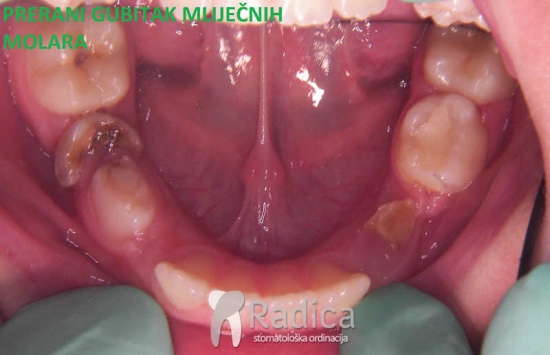

1. Prerani gubitak mliječnih molara. Lingvalnim lukom spriječavamo pomak trajnih molara naprijed.